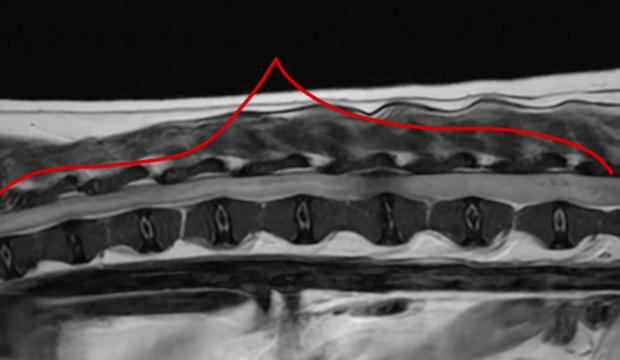

身体検査で臀部の膨らみを確認。触診・画像検査で腸と前立腺の会陰部脱出が認められた。

| 会陰ヘルニアは、高齢の未去勢の雄犬に多い疾患です。会陰(お尻の周囲)部の筋肉間がゆるんで腹部臓器がお腹の中から皮下にとび出して(ヘルニア)しまう病気です。 この症例は、腸、膀胱、前立腺が皮下へとび出しており、もう少しで排尿ができなくなり致命的な状況になるところでした。 本症例は人工メッシュを用いて会陰ヘルニア整復手術を行いました。術後は排便排尿もスムーズにでき、経過も良好です。なお、会陰ヘルニアは再発率が高い疾患であり、術後も日常ケアや経過観察が必要となります。 |